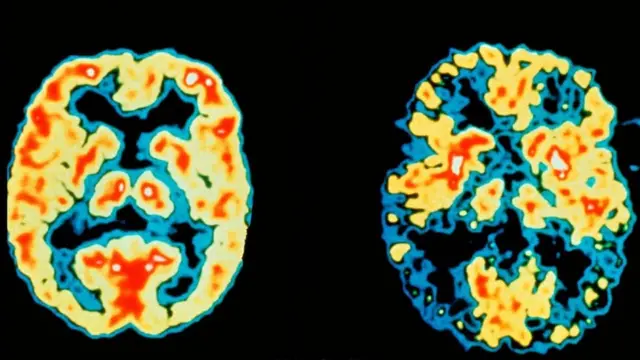

Son yıllardaki araştırmalar, yaşlanmaya bağlı hafıza kaybının ve hafif bilişsel yetersizlik ve demansın (bunama) azaltılmasında uykunun önemini ortaya koydu. Hayvanlar üzerinde yapılan çalışmalarda, beyindeki amiloid gibi atık maddelerin uyku sırasında temizlendiği görüldü. Beyinde amiloid birikmesi Alzheimer'a bağlı demansın patolojik özelliklerinden biridir. Uyku ile "beyin yıkama", yani beyindeki zararlı maddelerin uyku sırasında atılması konusu son zamanlarda yoğun ilgi görüyor.

Kaynak, DR ROBERT FRIEDLAND/SCIENCE PHOTO LIBRARY